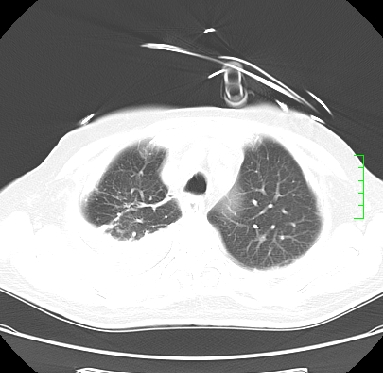

icu病人,几天都没明确诊断。m,76y,咳嗽、咳痰1周,伴气促,右胸痛入院,pe:t38.3c p135 r25 bp135/85。双肺可闻及大量湿罗音,心、腹未见明显异常。诊断:1心衰?2肺部感染?3冠心病?

11号ct

1)两肺感染性病变(右肺下叶肺脓肿可能)。2)双侧胸腔积液,以右侧为甚。

考虑双肺感染、右肺下叶肺脓肿伴双侧胸腔积液。

考虑双肺感染、右肺下叶肺脓肿伴双侧胸腔积液,肺水肿。

考虑:双肺感染、右肺下叶肺脓肿,双侧胸腔积液,肺水肿.请结合临床.